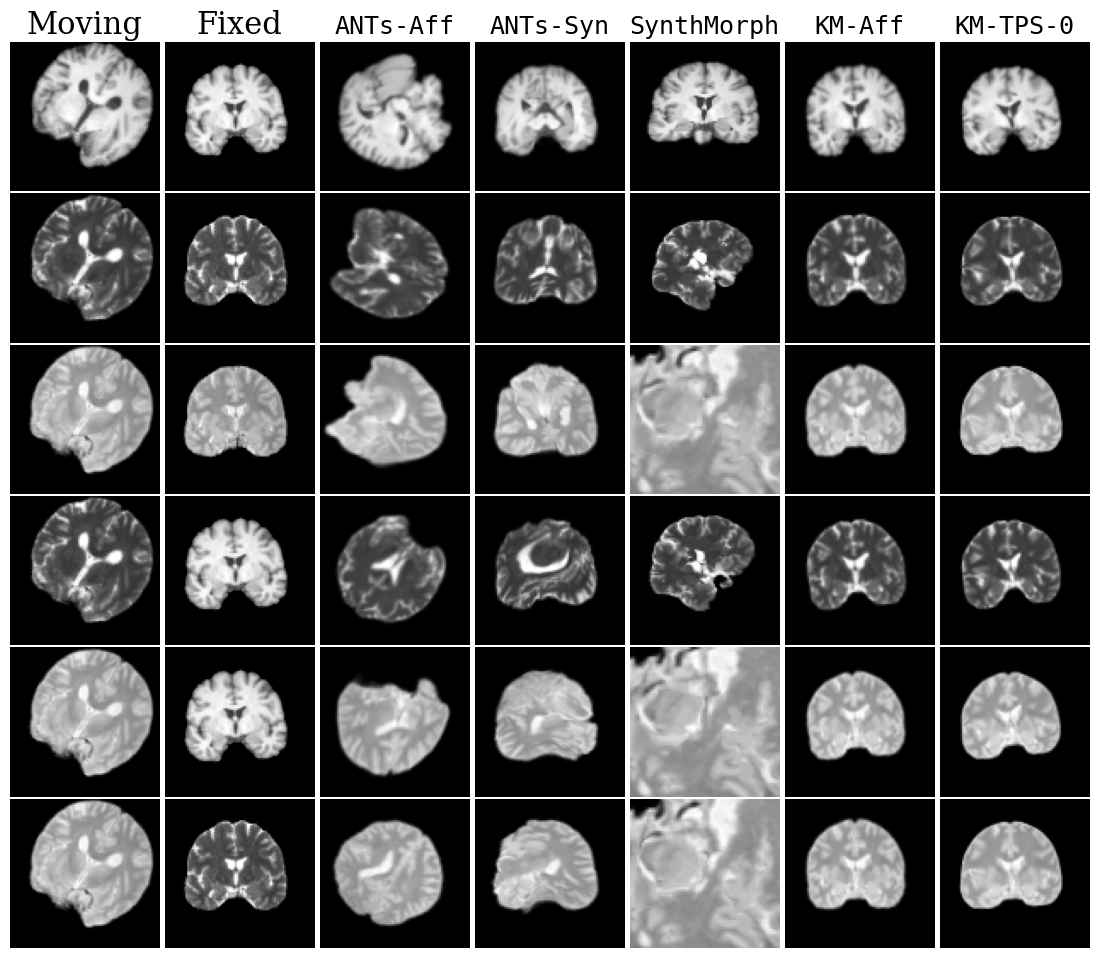

Refer to caption

Fig. 18: Qualitative results for all models. Moving image is misaligned by 45° in each dimension. DLIR results are omitted to save space.